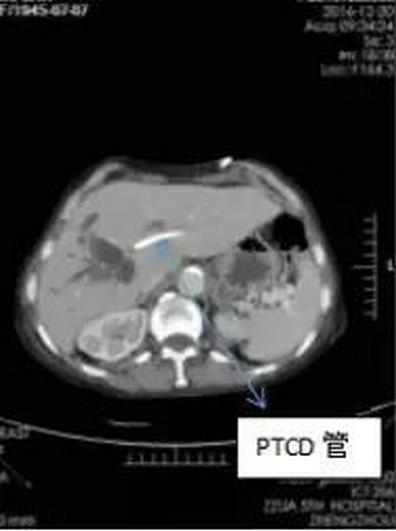

李晓勇教授根据病人情况多次组织科室病例讨论,认为患者年龄大,黄疸较重,肝功能较差,高胆红素血症,严重低蛋白血症。肿瘤已侵犯门静脉,不可能切除,决定先进行PTCD引流,待肝功能好转、全身营养状况改善后可行纳米刀消融手术治疗。接受PTCD术后10余天樊奶奶的黄疸减轻,身体条件较之前好转,具备了行纳米刀消融手术的条件。

PTCD术后